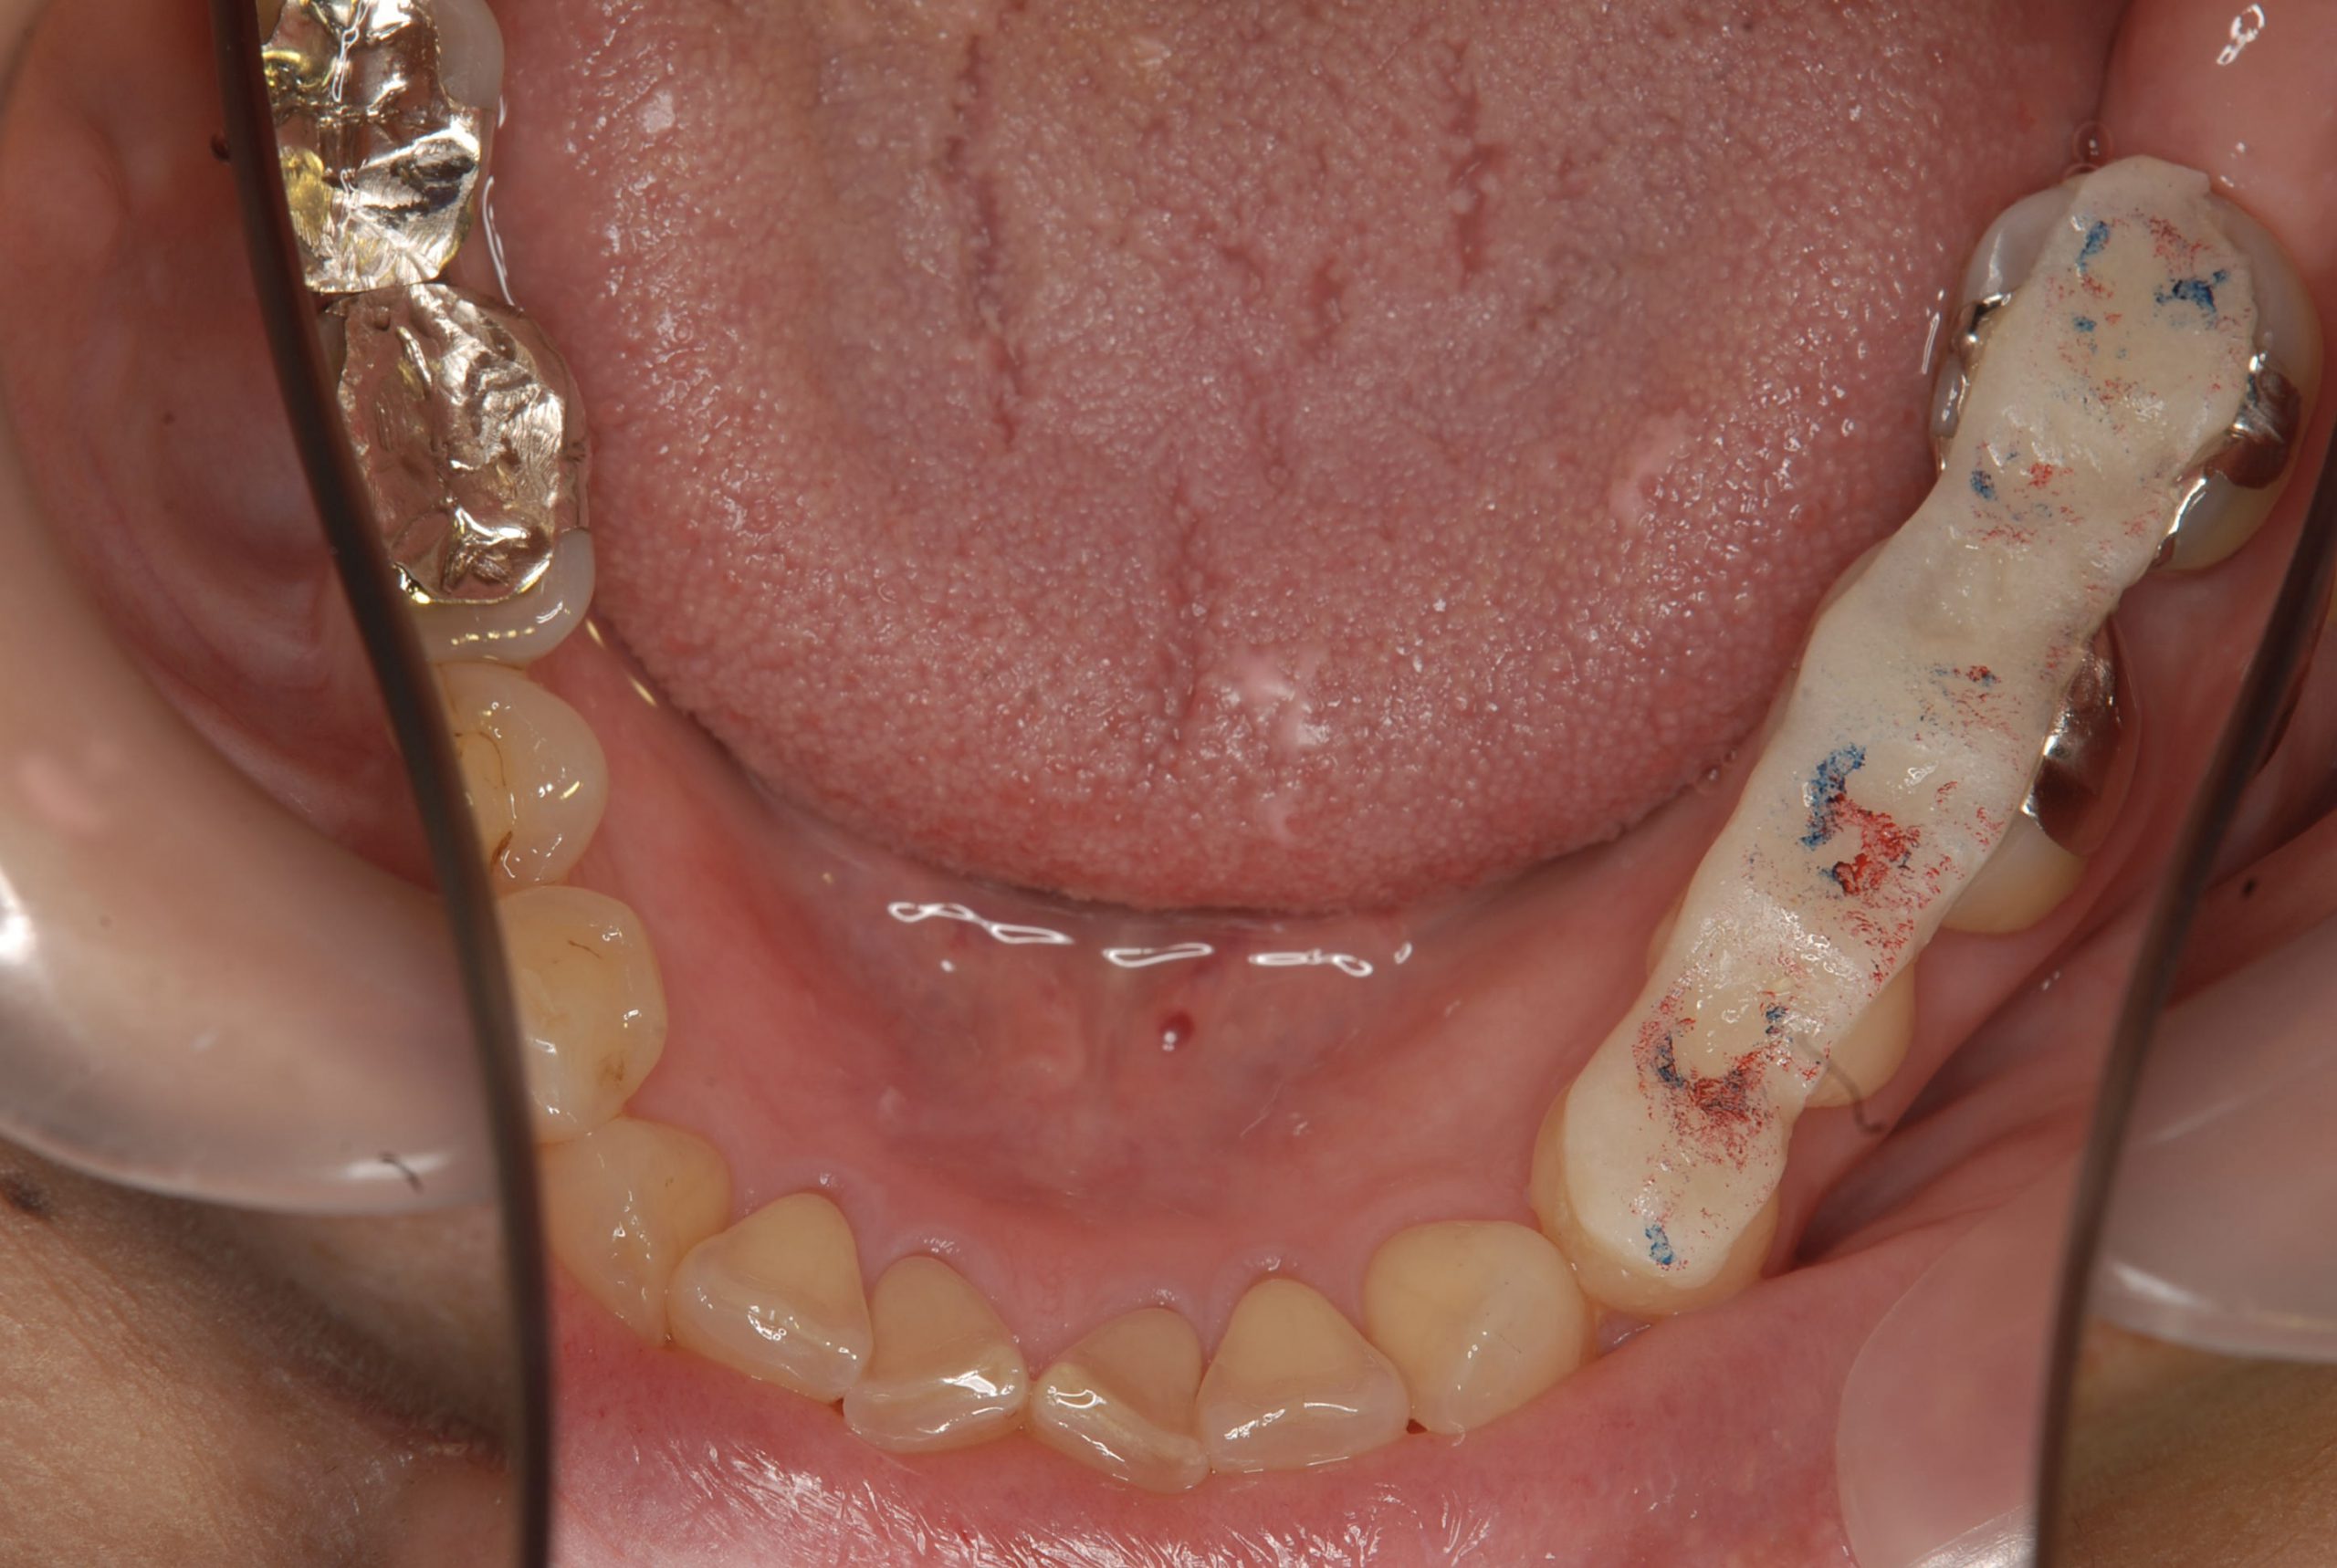

レジンアップや、夜間時装着の前方スプリントなどの治療方法で痛みの寛解に至り、

本日がファイナル補綴物のセットに

前歯の接触がない為、歯冠高径と前方基準となるジグを治療時には装着し確認しながら行われたそうです。基準をしっかり把握する『診断』を出来る医師はどのくらい存在するのでしょうか?私は、こんな治療を見るたび彼の治療に対する熱意と執念(笑っ)に敬服します